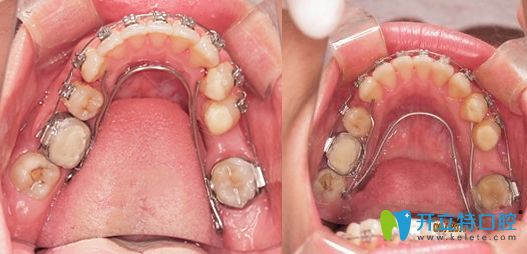

牙齒矯正擴牙弓和拔牙對比圖

擴弓矯正的前后效果對比圖